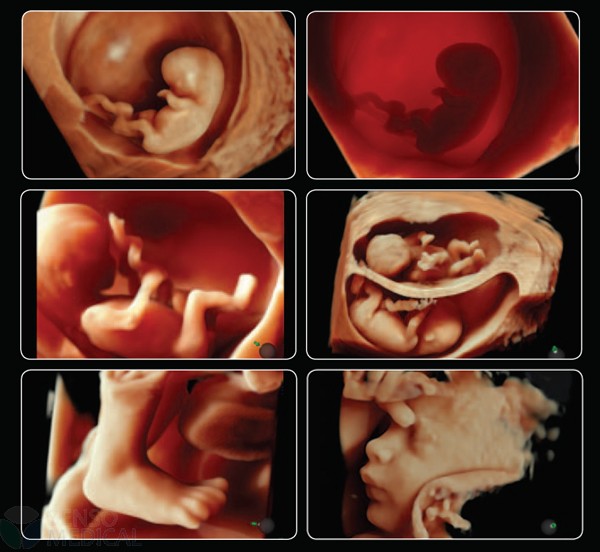

Ultrasonograf GE Voluson E8 Expert wersja oprogramowania BT13 (UISApp 13.0.6.254) 4D HDLive –

System Voluson E8 Expert to unikalne rozwiązanie w zakresie diagnostyki chorób kobiecych oferujące wysoką jakość obrazowania w trybach 2D i 3D/4D oraz uproszczone procedury usprawniające przepływ pracy i zapewniające najwyższą jakość badań. Więcej szczegółów, mniej wysiłku!

Oprócz najnowocześniejszych opcji obrazowania w usg 2D 3D 4D oraz opcji dopplerowskich posiada także funkcję ELASTOGRAFII.